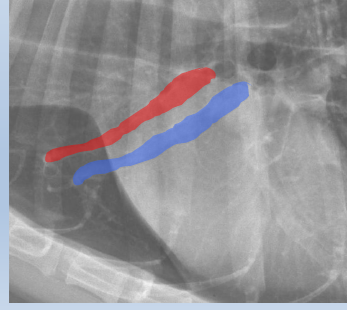

Arteries up and away

Veins ventral and central

Red Cupula

Blue Crura